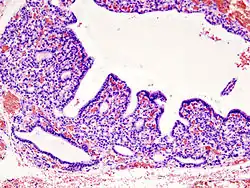

Nadczynność tarczycy, hipertyreoza (łac. hyperthyreosis lub hyperthyreoidismus) – stan chorobowy będący wynikiem nadmiernej produkcji hormonów tarczycy. Rzadziej nadczynność tarczycy powstaje na skutek leczenia nadmiernymi dawkami hormonów tarczycy, zaburzeń w ich obwodowym metabolizmie lub upośledzonej czynności wiążących je receptorów.

Choroba z grupy chorób autoimmunologicznych. Organizm zaczyna produkować immunoglobuliny klasy IgG, które – naśladując fizjologiczne działanie hormonu tyreotropowego przysadki (TSH) – pobudzają tarczycę do produkcji hormonów tarczycy – tyroksyny i trójjodotyroniny. Obecność wymienionych przeciwciał i nadmiar hormonów tarczycy we krwi powoduje wystąpienie objawów klinicznych. Cechami charakterystycznymi towarzyszącymi chorobie jest obecność wola miąższowego i zmiany oczne tzw. orbitopatia tarczycowa (oftalmopatia). Choroba Gravesa-Basedowa jest najczęstszą postacią nadczynności tarczycy występującą u dzieci[1][2].

Spowodowane są powstaniem w miąższu tarczycy guzka lub guzków, które produkują hormony tarczycy, jednakże są autonomiczne, czyli nie podlegają fizjologicznej kontroli sprzężenia zwrotnego zależnego od TSH. Guzki prawie zawsze są łagodne, jednakże w wyniku długotrwałego przebiegu mogą ulec przemianie złośliwej. Nigdy nie występują zmiany oczne pod postacią oftalmopatii.